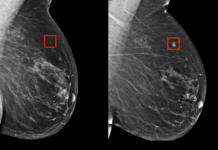

Yapay zeka meme kanserini radyologlar kadar etkili bir şekilde tespit edebiliyor. ,

Yapay zeka meme kanseri tespitinde başarılı oldu

İngiltere Lund Üniversitesi’nden bilim insanları, yapay zekanın tespit...